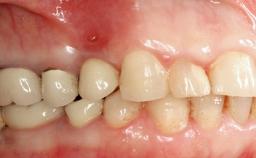

Prosthesis Type FDP

Defining Characteristics Up to three missing teeth to be replaced with an implant-borne restoration or restorations

Loading Protocol Conventional or early

Retention Screw-retained, with splinted implants Screw-retained, with splinted implants